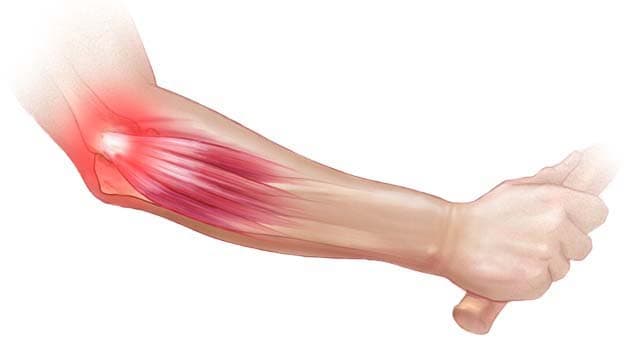

Tenisçi Dirseği (Lateral Epikondilit) Nedir?

Tenisçi dirseği, dirseğimizde üç kemik bir araya gelerek bir eklem oluşturur. Bu kemikler, kol kemiğinin alt ucu ve ön...